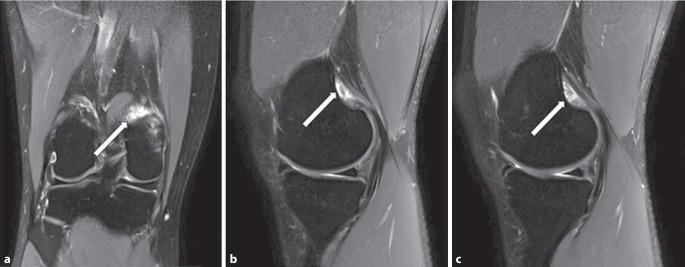

本病例报告介绍了一名32岁男性休闲运动员的临床表现和治疗方法,他表现为持续4个月的膝盖疼痛,没有外伤史。患者行走时间歇性疼痛,尤其是长时间坐着后,半月板检查呈阳性。然而,他能够毫无痛苦地参加体育活动。磁共振成像(MRI)显示腓肠肌内侧头部分撕裂,证实了诊断。保守治疗,包括休息、物理治疗和逐渐恢复体育活动,导致明显的症状改善。本病例强调了考虑罕见损伤的重要性,如腓肠肌内侧头的孤立撕裂,在持续的膝关节疼痛和半月板症状的患者中,即使没有创伤事件。先前关于这种特殊损伤的报道很少,表明其罕见性,并强调需要进一步了解和记录。

This case report presents the clinical findings and management of a 32-year-old male recreational athlete who presented with ongoing knee pain for 4 months, without a history of trauma. The patient experienced intermittent pain during walking, particularly after prolonged periods of sitting, and exhibited positive findings on meniscus tests. However, he was able to participate in sports activities without pain. Magnetic resonance imaging (MRI) revealed a partial tear of the medial gastrocnemius head, confirming the diagnosis. Conservative treatment, including rest, physical therapy, and a gradual return to sports activities, led to significant symptom improvement. This case highlights the importance of considering rare injuries, such as isolated tears of the medial gastrocnemius head, in patients with persistent knee pain and meniscal symptoms, even in the absence of traumatic events. Previous reports on this specific injury are sparse, indicating its rarity and underscoring the need for further understanding and documentation.